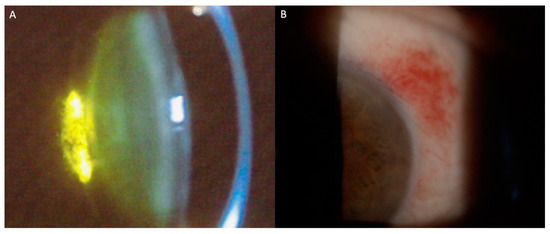

- Türkoğlu, E.B.; Öcal, O. Anterior segment optical coherence tomography findings in leukemic iris infiltration. Photodiagn. Photodyn. Ther. 2022, 37, 102578. [Google Scholar] [CrossRef] [PubMed]